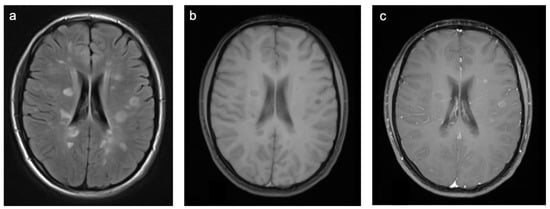

Group 2 consisted of 30 patients. Eight patients (27%) suffered from perinatal asphyxia; one of them was born preterm. Ten patients (33%) were diagnosed with periventricular leukomalacia (PVL); six of them were born preterm and two had co-occurring intraventricular hemorrhage (IVH). Ten patients (33%) showed signs of ischemic stroke. Eight of these strokes were of obscure or of unknown origin (cryptogenic). One was suspected to be cardio-embolic in a patient with a congenital heart disease with a ventricular septal defect in inherited Xq24 microdeletion syndrome and one as associated with sickle cell disease. The remaining two patients (7%) suffered from a cerebral venous sinus thrombosis with venous outflow obstruction leading to ischemia. A representative case is shown in Figure 4. In total, 60% of patients were female and the mean age was 7.8 years (min 3 days; max 18.4 years). A total of 57% of patients were examined with contrast-enhanced MRI and 12% of those examinations showed at least one enhancing lesion. WMSAs in this group of patients were localized supratentorial only. A total of 43% of patients had multifocal WMSAs.

Figure 4. Representative case “Non-genetic hypoxic and ischemic insults”: term-birth asphyxia. DWI/ADC (a,b), T2W (ce), FLAIR (f) sequences. Neonatal resuscitation after severe term-birth (40 weeks) asphyxia in a three-day-old girl. (ac). Treatment with therapeutic hypothermia. MRI shows predominantly white matter injury as one of the patterns identified in term-birth asphyxia [20]. The same girl examined again at the age of four years (df). MRI shows periventricular signal hyperintensities in T2W/FLAIR sequences.